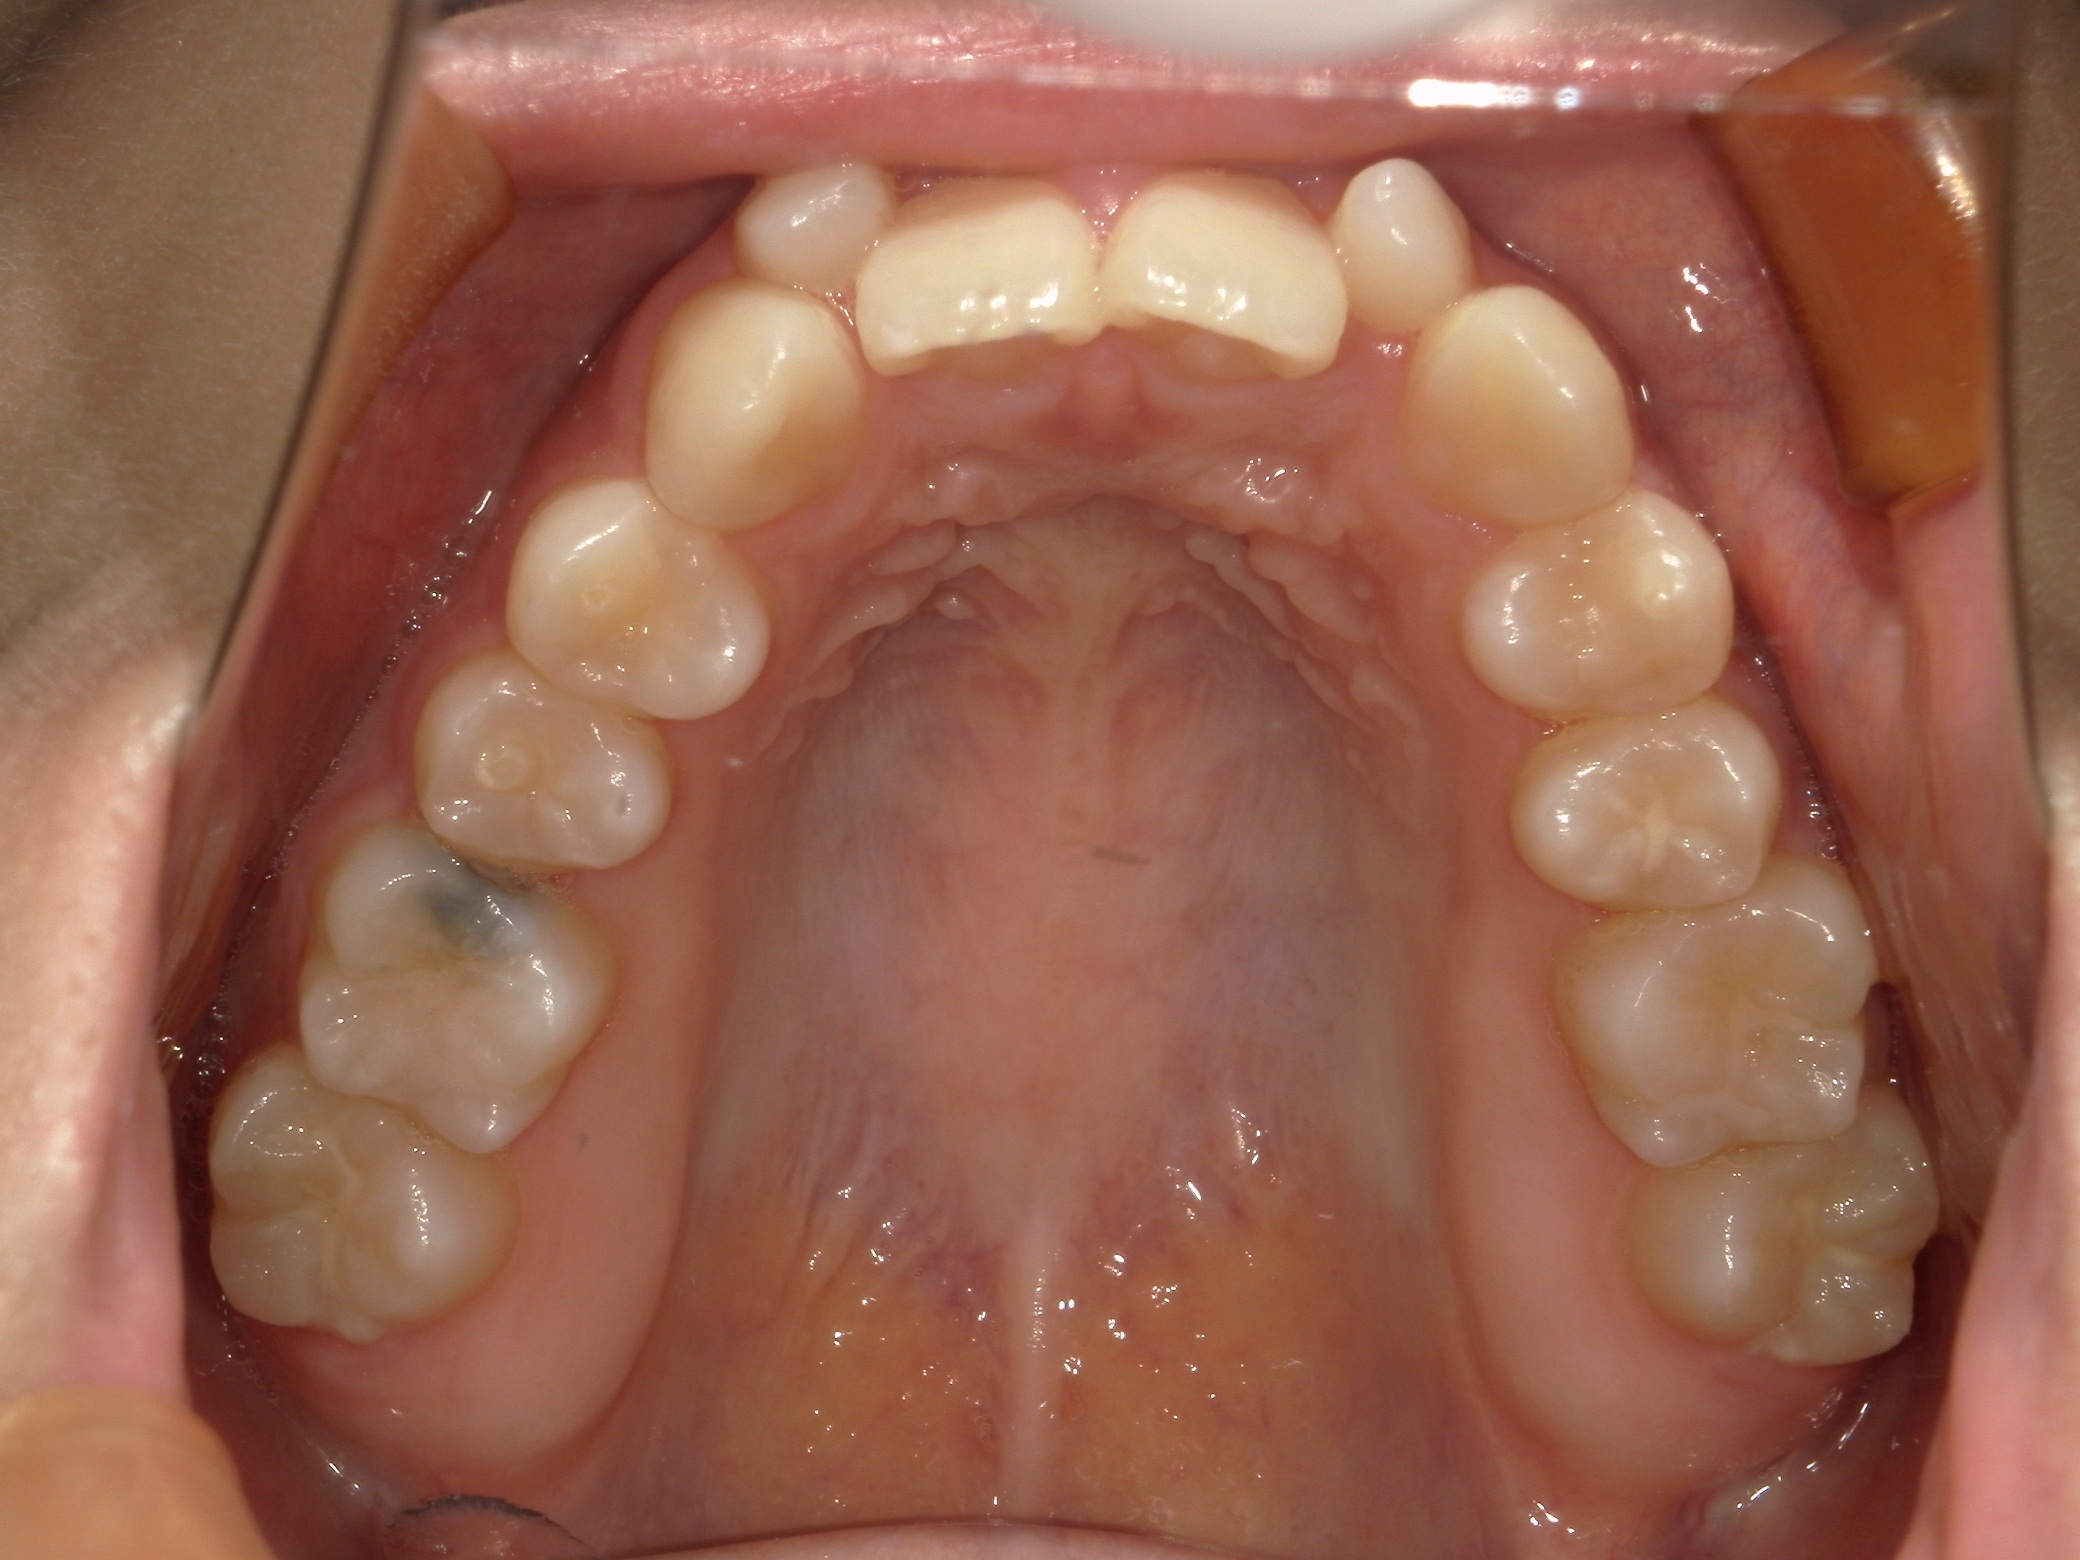

口内上

治療前

また、上の前歯が2本、矮小歯(他の歯に比べて大きさが極端に小さい歯)でした。

上は矮小歯を、下は横の歯を抜いて治療を行いました。

上の歯は2番の歯を犬歯で代替しているので、上下の大きさの違いが出るのですが、不自然にならないよう幅をわずかに調節して仕上げています。